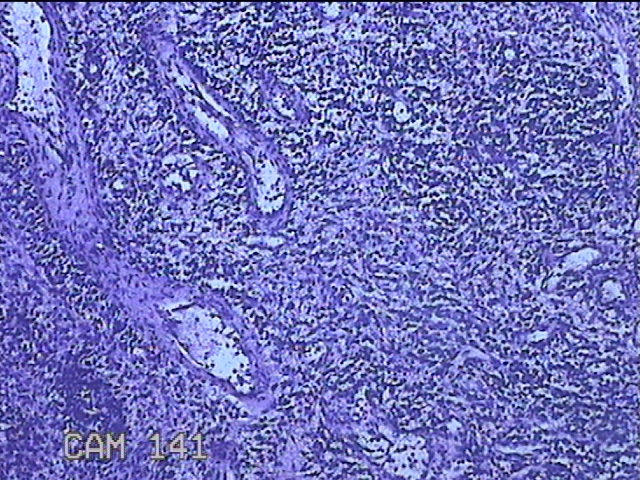

性别

女

年龄

36岁

临床诊断

宫颈赘生物

一般病史

发现宫颈赘生物1个月。

标本名称

大体所见

灰白暗红色肿物1x0.7x0.2cm一个,表面糜烂。

图2